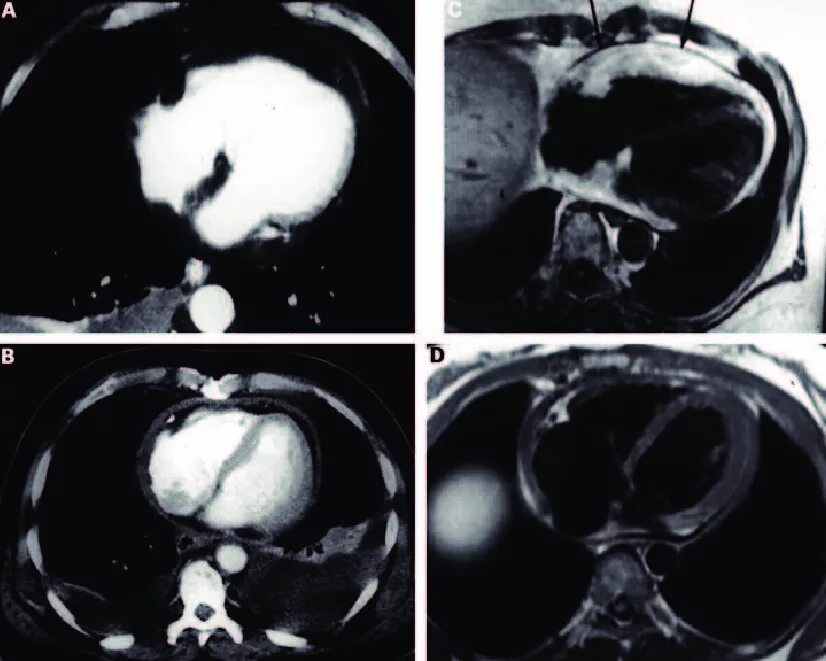

Normal abnormal